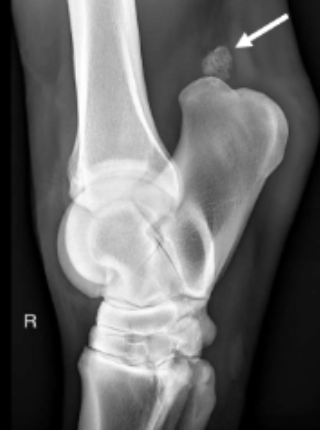

A 12 year horse with mild lameness had a 5mm diameter, oval, firm mass between the gastrocnemius and deep digital flexor tendon. Histology showed a focus of mineralisation amongst fibrous scar tissue, and some mild lymphocytic and plasmacytic inflammation. No other abnormalities were found in the horse.

Image: Radiograph showing region of mineralisation (arrow).

What is the most likely pathological process causing this lesion?

A

Dystrophic calcification